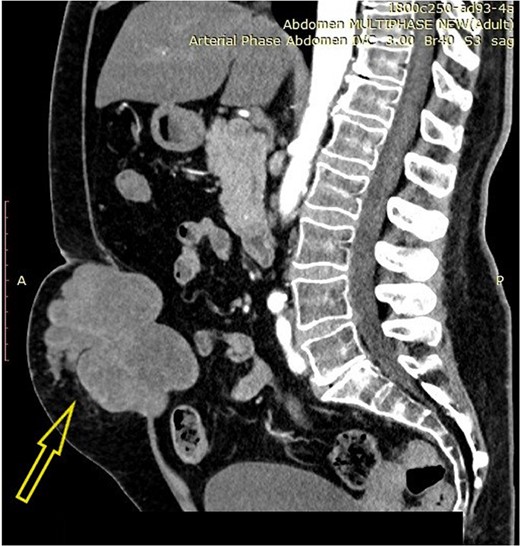

A 58-year-old female patient (smoker) complained of abdominal wall pain and a palpable tumor, 3 months before presenting in the outpatient ward. Previously diagnosed comorbidities were hypertension, hypothyroidism, and Type II diabetes mellitus. Preoperative serum parameters were within the normal range, except for the serum glucose level (15.04 mmol/L). Contrast-enhanced abdominal computerized tomography revealed a tumor with expansive growth toward the subcutaneous tissue and the peritoneum, with origin from the left rectus abdominis muscle. The tumor was described as multinodular, lobulated, well-demarcated, relatively homogenous mass with dimensions 11 × 8.5 cm (Fig. 1). Surgical excision of the lesion with abdominal wall reconstruction was indicated. Intraoperatively, wide excision with partial resection of the involved abdominal wall muscles was performed (Fig. 2). Primary abdominal wall reconstruction with a nonabsorbable suture was performed (without the use of prosthetic mesh). Consecutive abdominal compartment syndrome did not develop. The postoperative period was uneventful and the patient was discharged on postoperative Day 5.

Contrast-enhanced abdominal computerized tomography with a tumor in the abdominal wall (arrow).